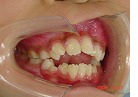

オープンバイト治療前